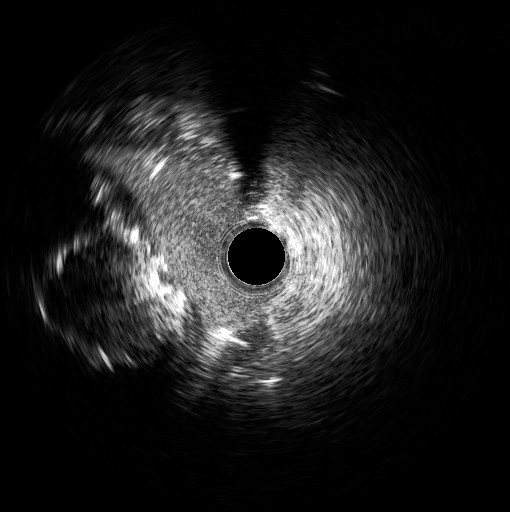

Four days later, the patient was admitted to the cardiology department because of exertional dyspnea. Because of the recent revascularization of the RCA, a new coronary angiography was performed. The angiography of the left system revealed no changes, but the RCA unveiled a nimble formation in the proximal part of the stented vessel (Figure 3, Video 3). An intravascular ultrasound was performed, which displayed the double-barrel configuration (Figures 4 and 5, Video 4) and the presence of a thrombus (Figures 6 and 7, Video 5). It was directly stented with an excellent angiographic result (Video 6). Two days postoperative, the patient was asymptomatic and discharged.